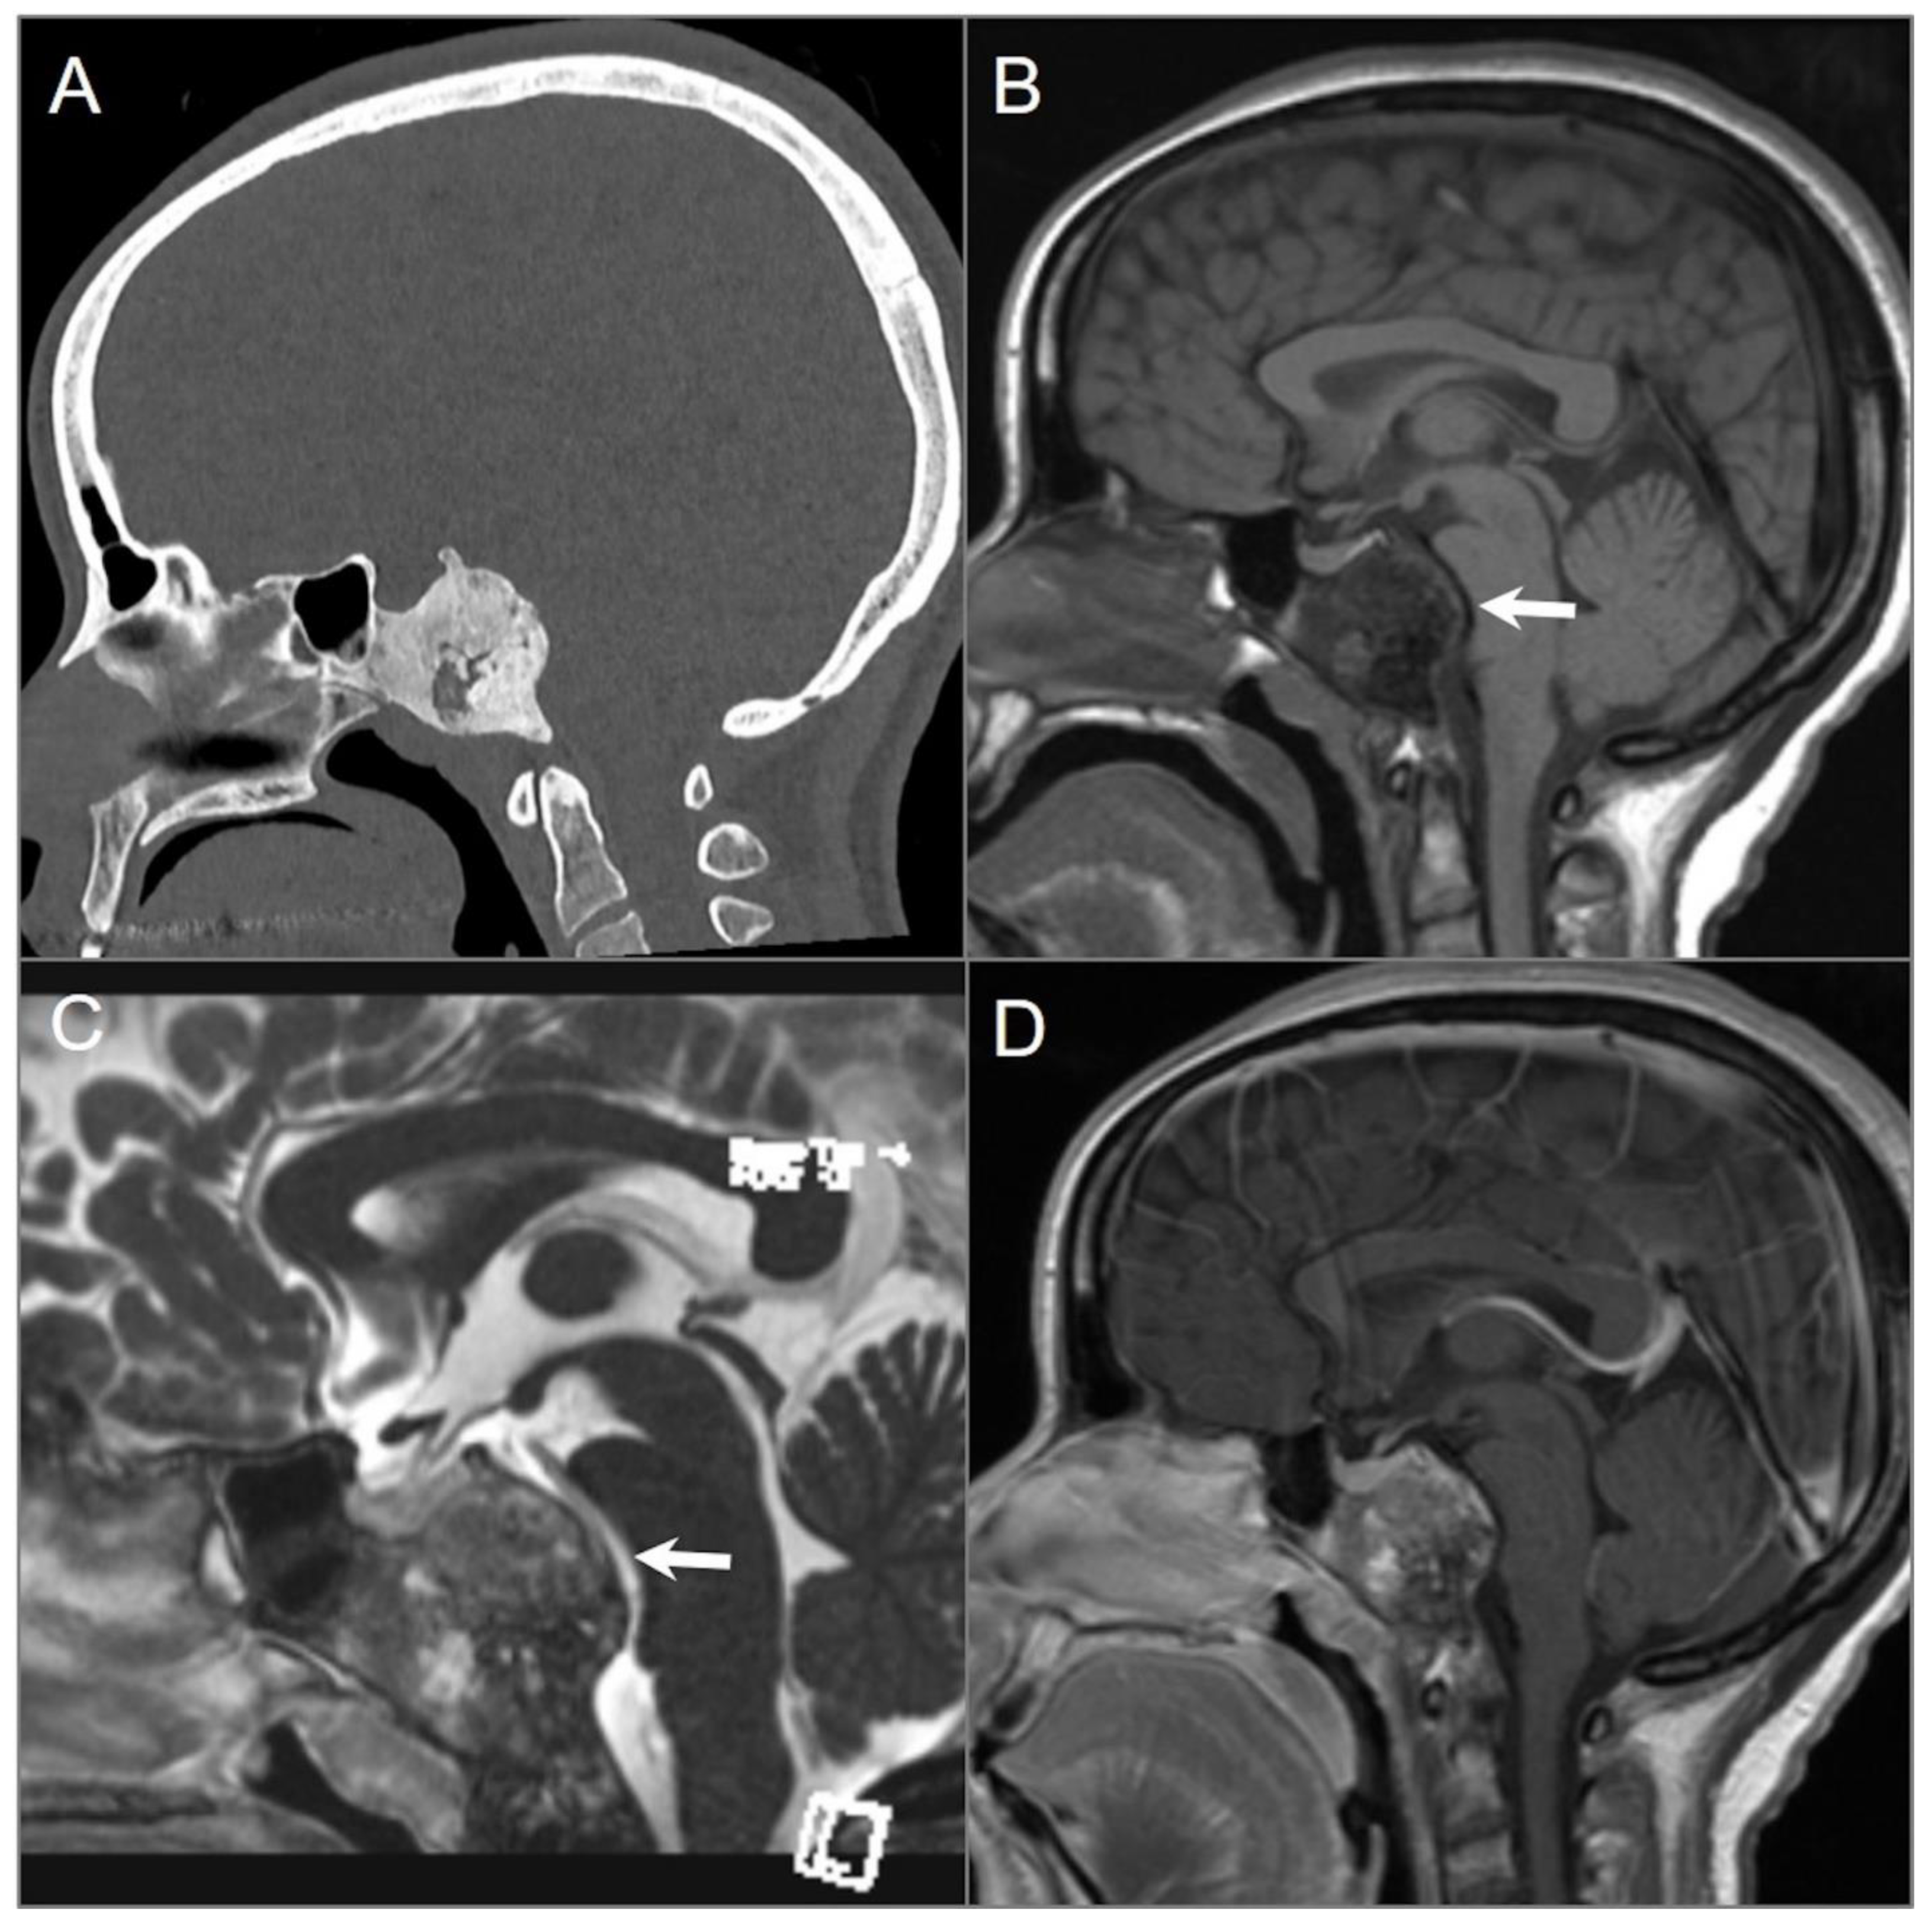

4.4.1. Chordoma